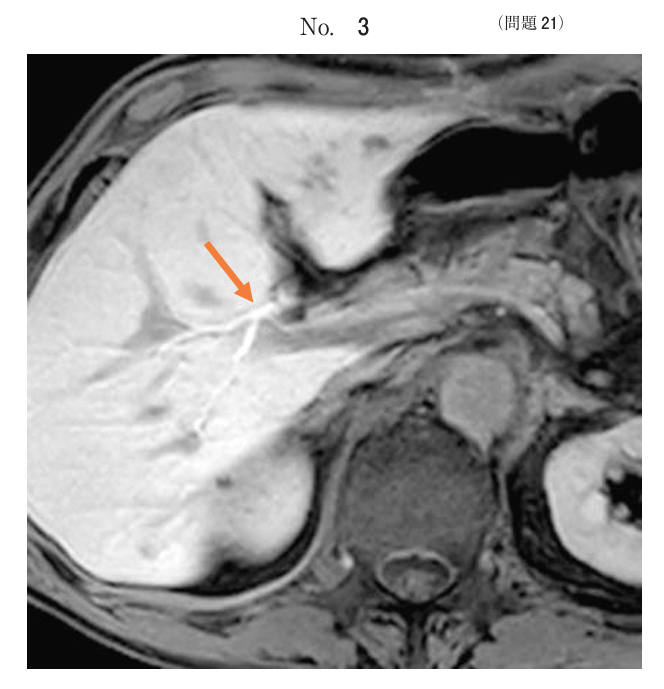

午前/問題21

Gd-EOB-DTPA投与20分後の腹部MRIの脂肪抑制T1強調像別冊No. 3 を別に示す。矢印で示す構造はどれか。

1.胆管

2.膵管

3.門脈

4.肝動脈

5.肝静脈